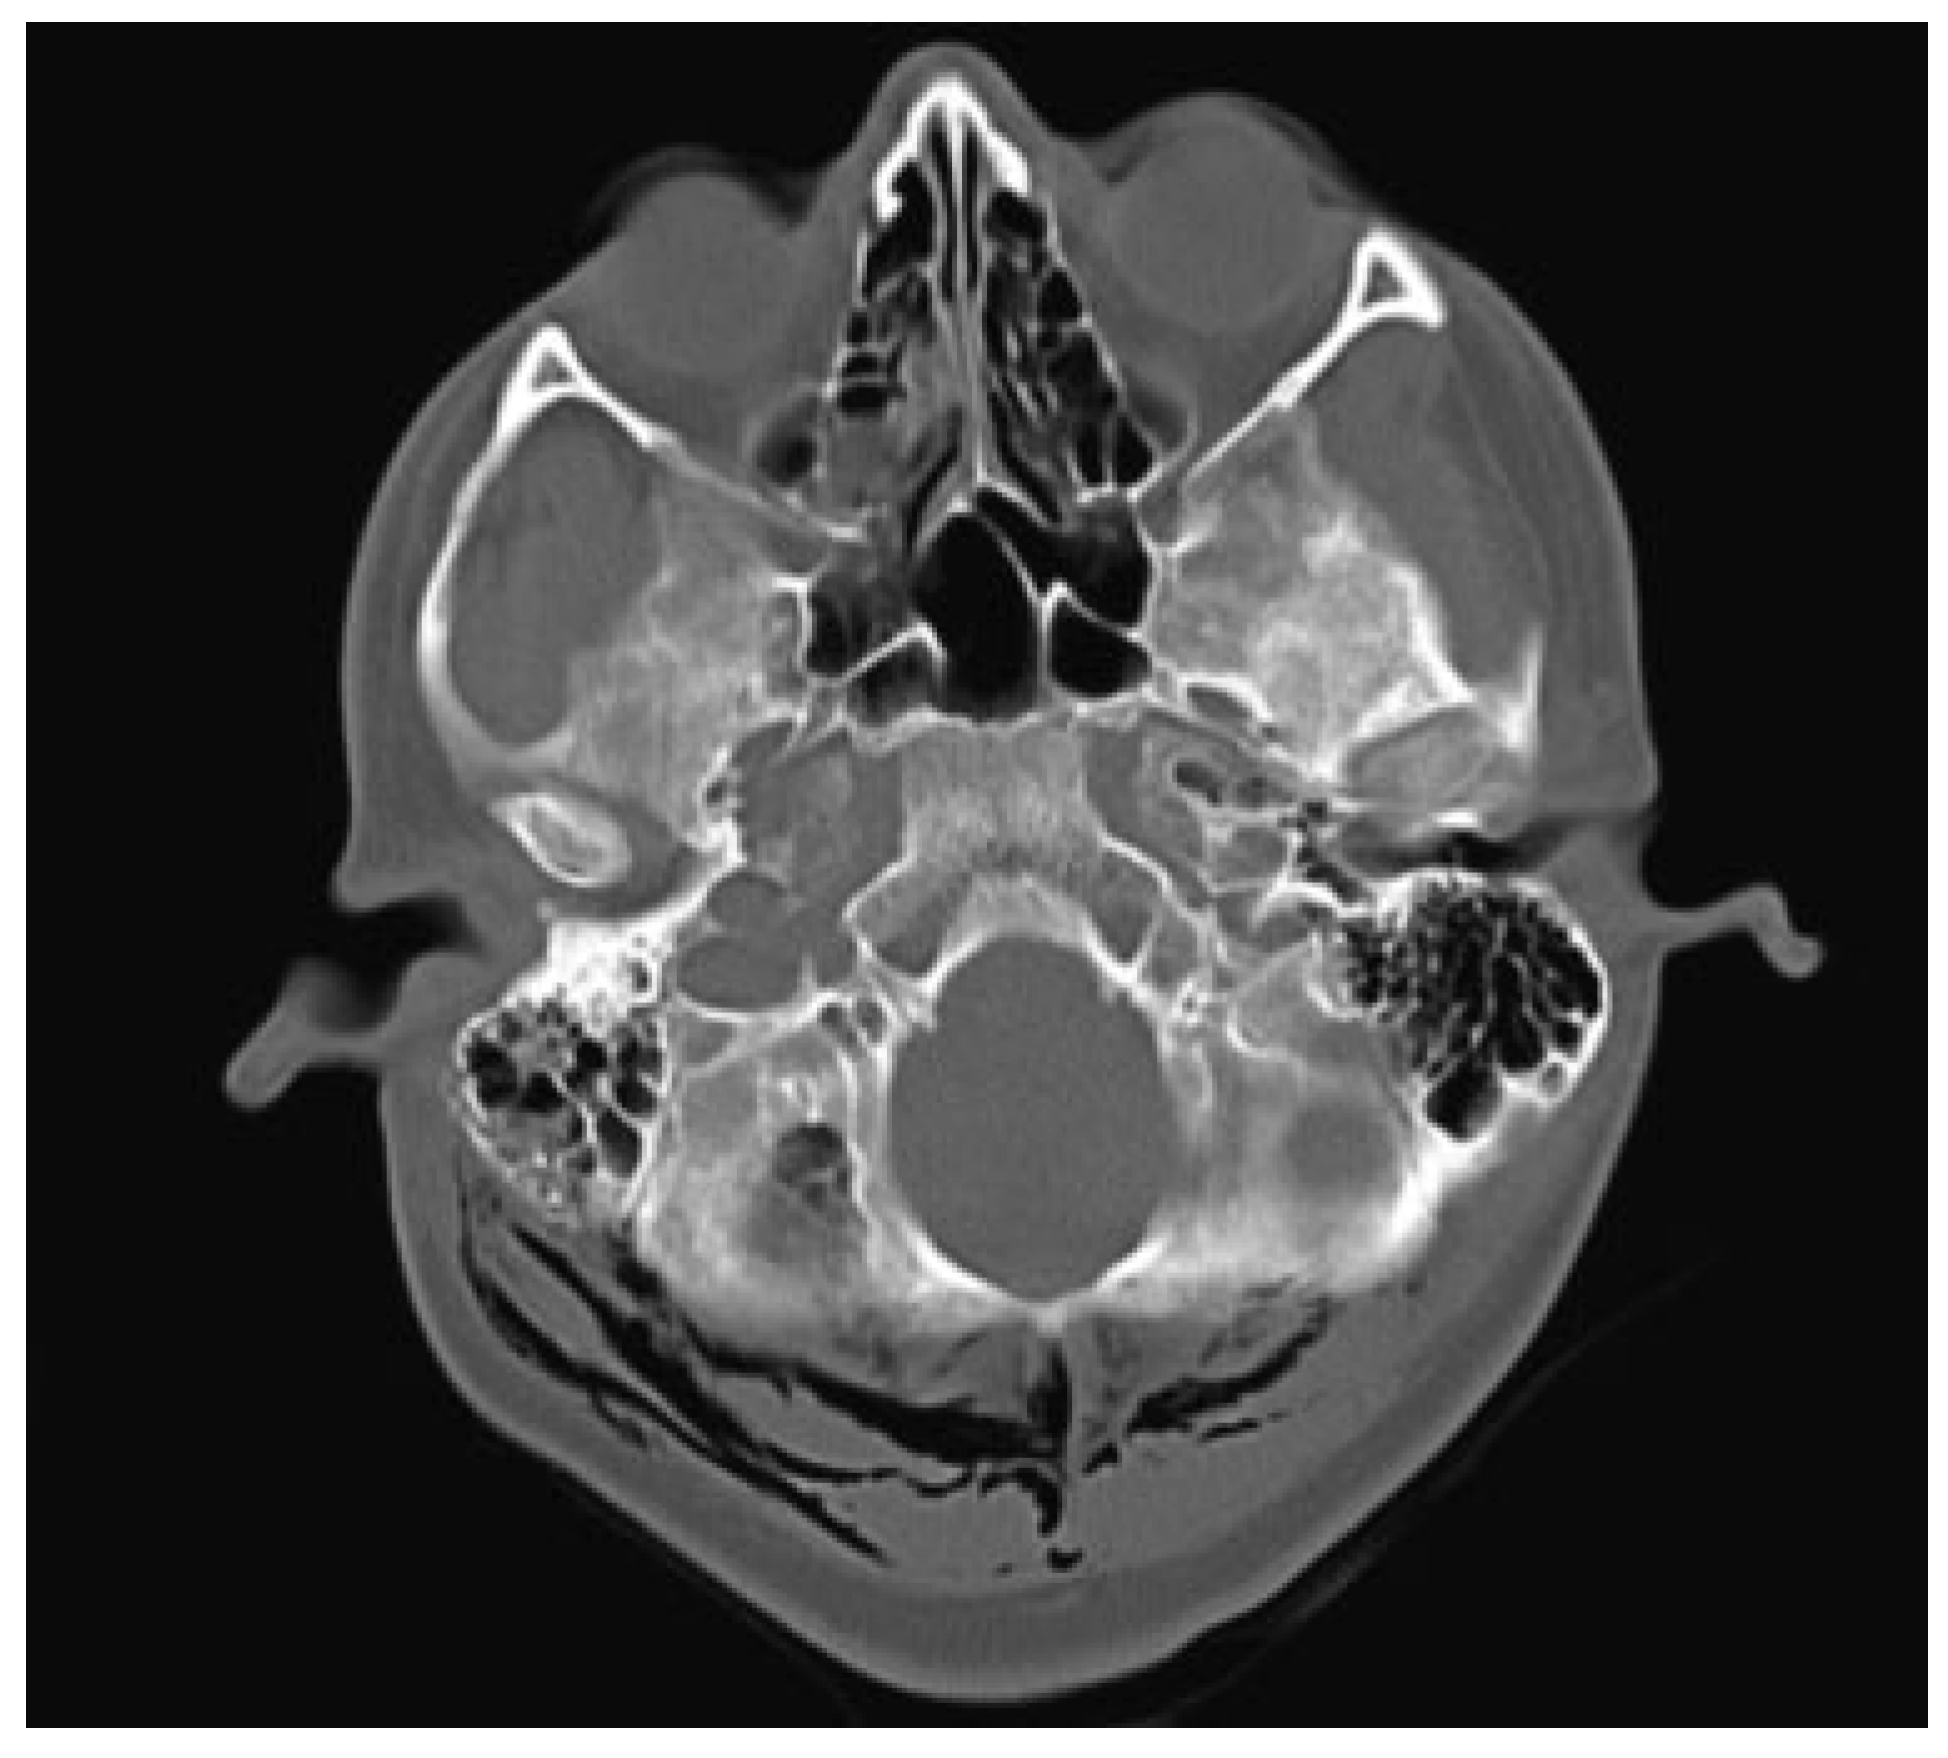

Temporal bone CT scan confirmed the presence of an isolated right comminuted mastoid process fracture with extensive right cervical emphysema extending from the fracture to involve the skull base, cervical soft tissues bilaterally, and adjacent musculature (Figure 2). There was opacification of the mastoid air cells surrounding the fracture lines. There was no violation of the otic capsule and ossicular alignment was normal.

Figure 2. Comminuted right mastoid fracture with air in inferior aspect of skull base and myofascial spaces of muscles attached to mastoid.